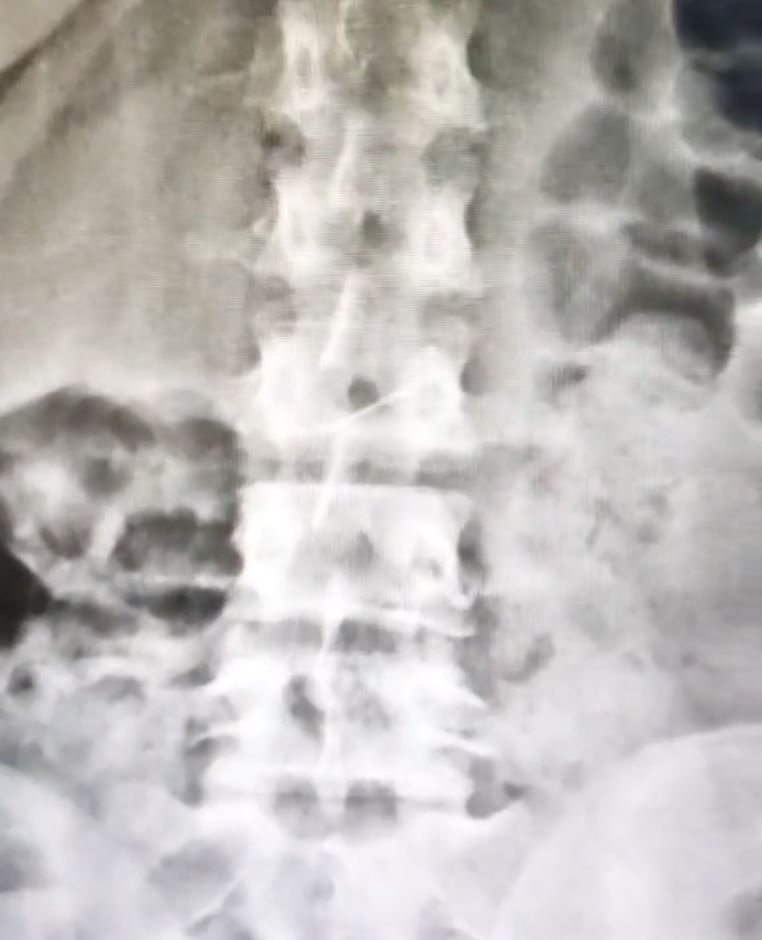

Menerusi klip video yang tular, jarum peniti ditemui dalam badan seorang wanita selepas menjalani imbasan sinar-X.

“Sekadar mengingatkan, ini imbasan X-ray seorang pesakit. Abdomen pesakit itu didiagnosis mempunyai corpus alienum atau kewujudan benda asing dalam tubuh.

“Ini kes wanita berhijab tetapi meletakkan jarum peniti di mulut. Akhirnya dia tertelan jarum itu.

“Nampak tak? Jarum dah masuk ke dalam usus. Kalau tersekat lebih 12 jam, pembedahan akan dijalankan,” kata perakam tersebut.